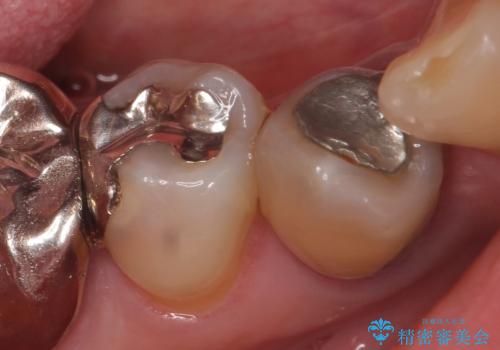

- 他院にて右下4番目の歯の再根管治療が必要だと言われた方の症例です。

再根管治療終了後、オールセラミッククラウンによる補綴を行いました。